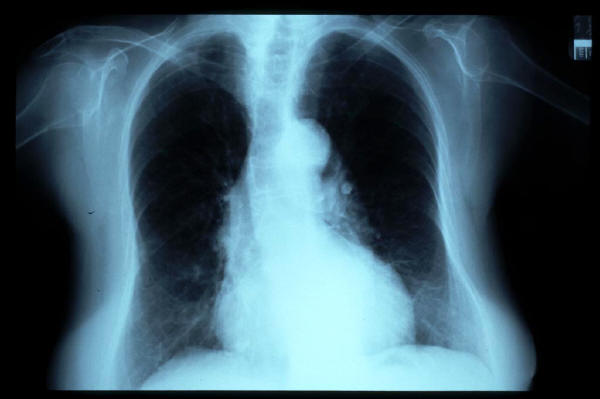

Fibrosis pulmonar. ICC.